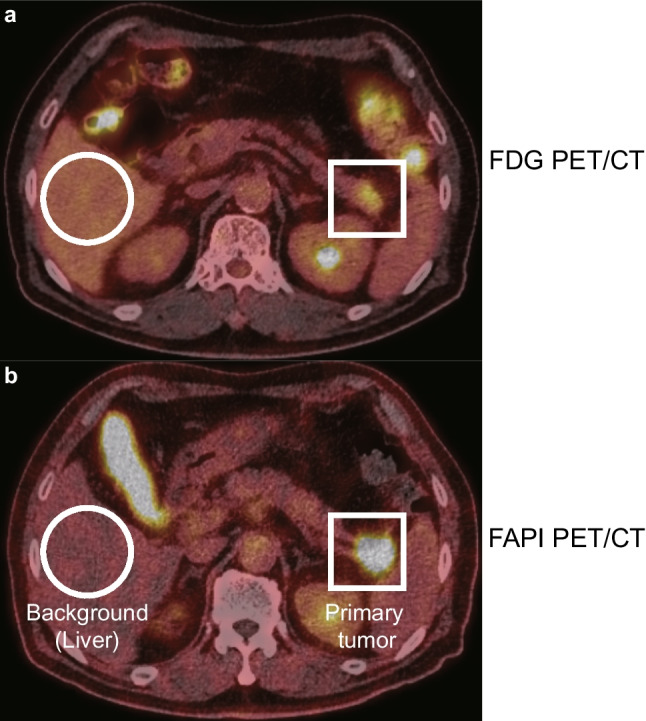

Results: [18F]AIF-FAPI-74 PET/CT showed a significantly higher maximum standardized uptake value than [18F]FDG PET/CT did in evaluating primary pancreatic lesions (median [interquartile range]; 12.6 [10.7-13.7] vs. 6.3 [4.8-9.2]; P < 0.001). In contrast, [18F]AIF-FAPI-74 PET/CT showed a significantly lower mean standardized uptake value than [18F]FDG PET/CT did in evaluating background organ (median [interquartile range]) 0.8 [0.7-0.9] vs. 2.6 [2.3-2.7]; P < 0.001). In addition, the sensitivity of [18F]AIF-FAPI-74 PET/CT in detecting metastatic lymph nodes was higher than that of [18F]FDG PET/CT (50.0% vs. 0.0%; P = 0.026).